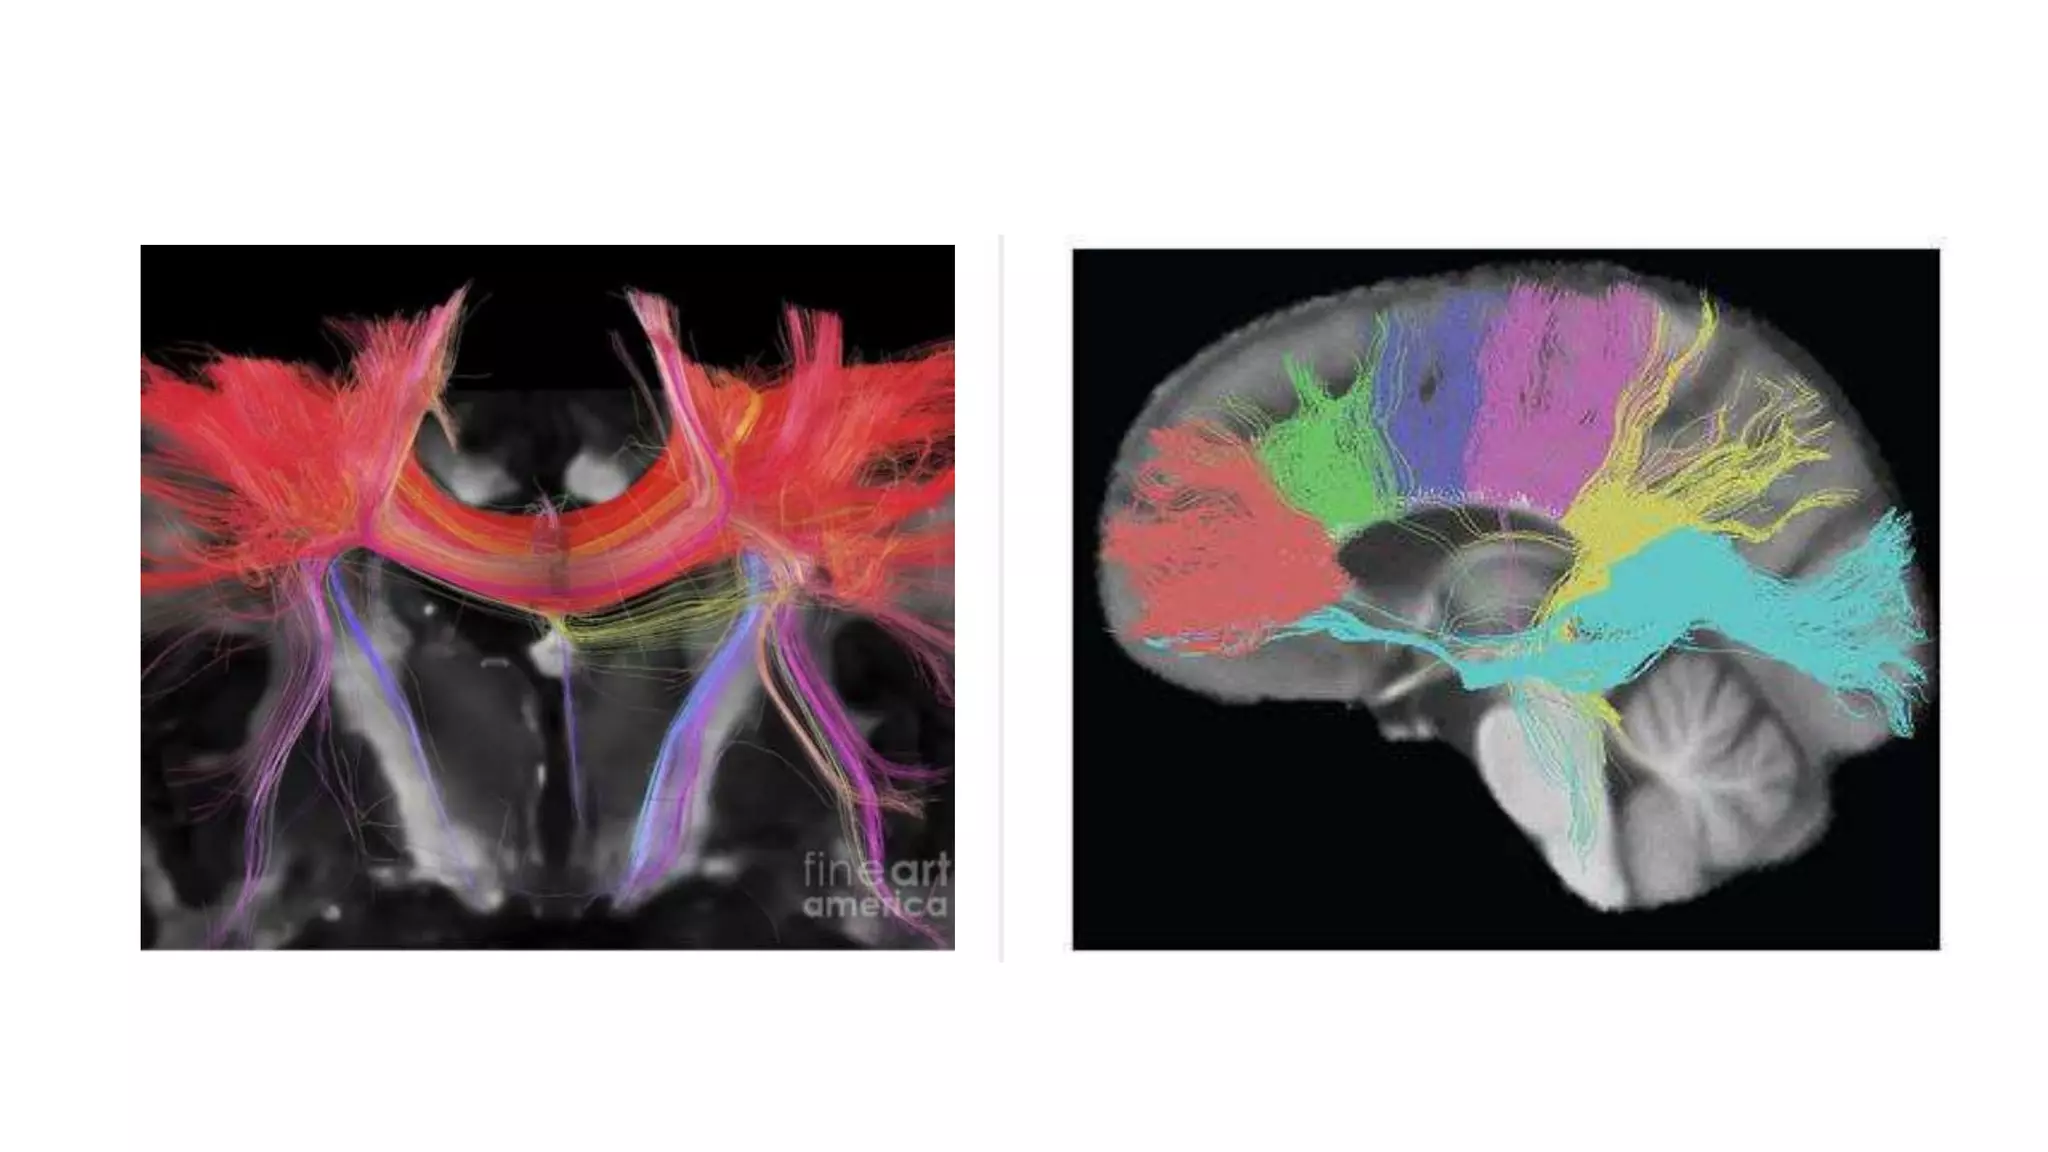

• #39 The tractogram pictured shows the nerve tracts from six segments of the corpus callosum, providing linking of the cortical regions between the cerebral hemispheres. Those of the genu are shown in coral, of the premotor – green, of the sensory-motor – purple, of the parietal – pink, of the temporal – yellow, and of the splenium – blue.[11]

• #40 llustration (A), gross dissection (B), directional map (C), and tractogram (D). The largest WM fiber bundle, the corpus callosum connects corresponding areas of cortex between the hemispheres. Close to the midline, its fibers are primarily left-right oriented, resulting in its red appearance on this DTI map. However, callosal fibers fan out more laterally and intermingle with projection and association tracts, resulting in more complex color patterns. Sagittal directional map of the corpus callosum (arrowheads) (A) and tractogram (B).